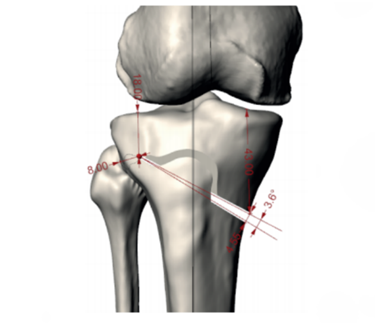

Describe Hueter-Volkmann’s Law.

= increased compression at the growth plate slows down longitudinal growth, increasing tension at the growth plate speeds up longitudinal growth.

What can be done surgically when someone has misalignment of the knee?

OSTEOTOMY

If younger than 40 then the bone can be cut across and hinnged open, and a growth plate added to straighten out the leg.